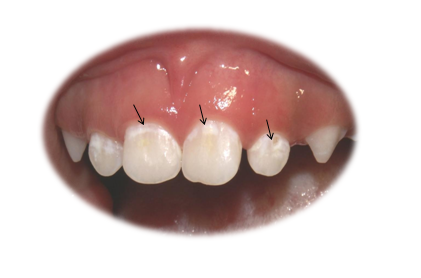

Kada postoji ravnoteža između ugradnje i izvlačenja minerala zubna gleđ je zdrava i normalne prozirne boje. Pojava beličaste boje(mrlja) prvi je znak da preovladava sredina pogodna za izvlačenje meinerala. Zubni kvar je posledica poremećene ravnoteže u kojoj dominira demineralizacija.